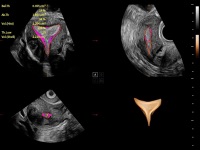

梦溪®P80以“关爱女性”为基石,提供全方位的解决方案,量身定制以满足女性的健康需求,涵盖妇科、生殖健康检查、产前筛查及产后康复等领域。

通过工作流协议、远程访问、自动探头激活和人体工程学优化设计等功能,旨在提高临床工作效率

提供解剖示意图、标准超声图像、扫查手法图和操作者实时检查图像,指导操作者进行标准切面的正确扫查。

与诊断项关联的测量、体标、注释项页面设置,支持专属页面设置的导入、导出,有利于医生更加便利地设置常用项